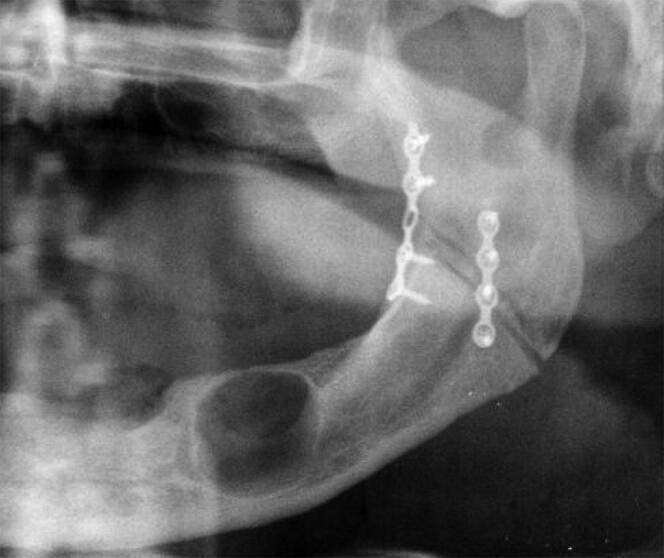

In December 2017, a decomposed unidentified body was found near the river Tronto in Teramo, Italy. The corpse was found without any identifying documents or specific personal belongings, except for a packet of cigarettes. The medical examiner determined a gastric perforation from the intake of hydrochloric acid to be the cause of death. A jar of muriatic acid found near the body led to suicide being considered the manner of death. The Penal Court in Teramo appointed two forensic odontologists to complete the postmortem assessment and collect dental data for personal identification. The corpse was found wearing a complete set of upper and lower dentures. The dental autopsy and 42 periapical X-ray images helped generate a biological profile of a man totally edentulous with upper and lower dentures, as well as an osteosynthesis with two plates and screws in the left ascending ramus of the mandible. In March 2018, the sister of a missing person reported the disappearance of her brother, and a presumptive identification was performed through visual recognition of the decomposed body. The sister confirmed the presence of two dentures and the location of the maxillo-facial surgery for the treatment of the fractured mandible. A complete dental autopsy was able to establish his identity without any DNA comparison needed. This case highlights the importance of performing a complete dental autopsy inclusive of dental radiographs, and its value in the identification of all unknown human remains even when totally edentulous. A complete dental autopsy should be performed in all cases of human identification.KeypointsDespite a corpse being edentulous, a complete dental autopsy can still be useful.Dental radiographs, such as bitewings, periapical images, panoramic radiographs, and CT scans, are recommended in all identification autopsies.

2017年12月,在意大利泰拉莫省的特龙托河附近发现了一具已腐烂的无名尸体。尸体被发现时没有任何身份证明文件或特定的个人物品,只有一包香烟。法医判定死因是摄入盐酸导致胃穿孔。在尸体附近发现的一罐盐酸使得自杀被认为是死亡方式。泰拉莫刑事法院指定了两名法医牙科学专家完成尸检评估并收集牙齿数据用于身份鉴定。尸体被发现时戴着一整套上下假牙。牙齿解剖和42张根尖周X光片有助于生成一名完全无牙但戴着上下假牙的男性的生物特征,以及在下颌骨左升支有两块钢板和螺钉的骨合成情况。2018年3月,一名失踪人员的姐姐报告了她弟弟的失踪,通过对腐烂尸体的视觉辨认进行了推定身份鉴定。姐姐确认了有两副假牙以及下颌骨骨折治疗的颌面外科手术位置。完整的牙齿解剖能够在无需任何DNA比对的情况下确定他的身份。这个案例凸显了进行包括牙科X光片在内的完整牙齿解剖的重要性,以及其在鉴定所有未知人类遗骸方面的价值,即使是完全无牙的情况。在所有人类身份鉴定案件中都应进行完整的牙齿解剖。要点尽管尸体无牙,但完整的牙齿解剖仍可能有用。在所有身份鉴定尸检中都建议使用牙科X光片,如咬合翼片、根尖片、全景片和CT扫描。